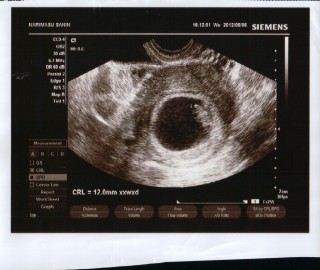

つわりが6週から始まり、食べても食べなくても気持ちが悪くて寝たきり状態で点滴しました(泣) 前回のエコーでは胎芽が見えなかったけど、今回はハッキリ見えて心拍も確認できました!まだ6ミリで小さいけどすごく嬉しいです(*^^*)

2週間の間にCRL11.6mm、

心拍も確認でき、

3週間後の検診までに母子手帳をもらってくるように言われました。